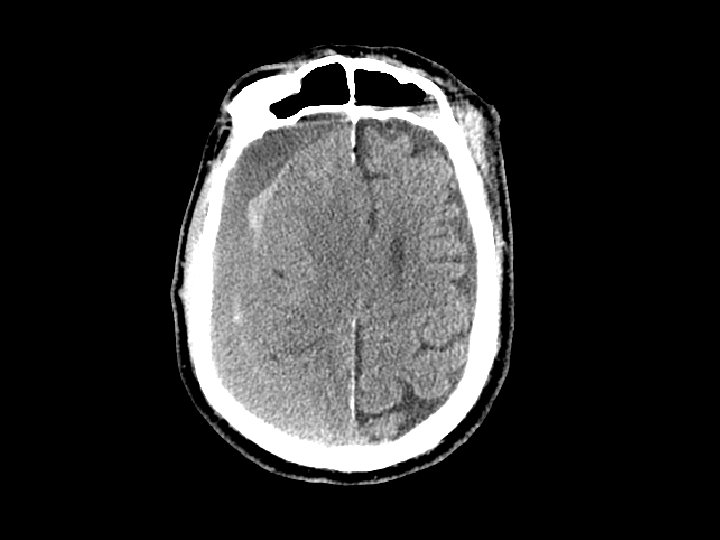

Tụ máu trong não • Tương tự như đụng dập não – Chấn thương nặng – Chảy máu trong não • Gặp ở thùy trán và thùy thái dương • Theo dõi diễn biến của xuất huyết • Có thể gây khối choán chỗ dẫn đến thoát vị não

Chảy máu não thất • Lụt máu não thất • Chảy máu não thất đơn thuần thông thường không gây hậu quả và không cần can thiệp điều trị

Chảy máu dưới nhện • Chảy máu dưới nhện và tụ máu là chấn thương thường gặp trên CT sau các sang chấn đụng dập • CT: xuất huyết ở các rãnh và hệ thống bể đáy • Thường kết hợp với tụ máu nội sọ • Đánh giá có thể chảy máu dưới nhện gây chấn thương (bệnh nhân xuất huyết tự nhiên và sau đó ngã) • Biến chứng: – Co thắt động mạch: 2 -3 ngày sau chấn thương